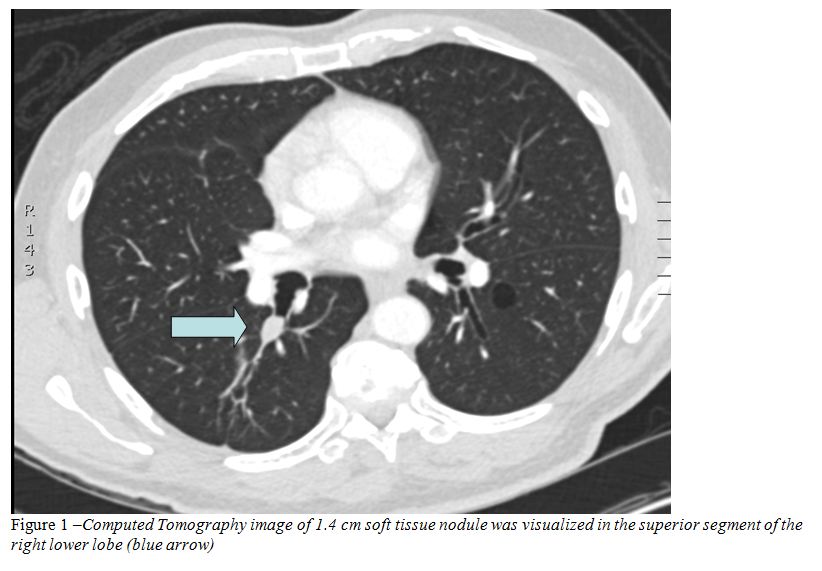

History

A flexible bronchoscopy was performed and a polypoid lesion was found occluding the orifice to the superior segment of the right lower lobe (Figure 2). A radial endobronchial ultrasound probe was used to further aid in the diagnosis of the lesion and it showed multiple echogenic foci of calcification (Figure 3). In order to diagnose the lesion and to restore patency of the airway an electrocautery snare was used to remove the lesion.